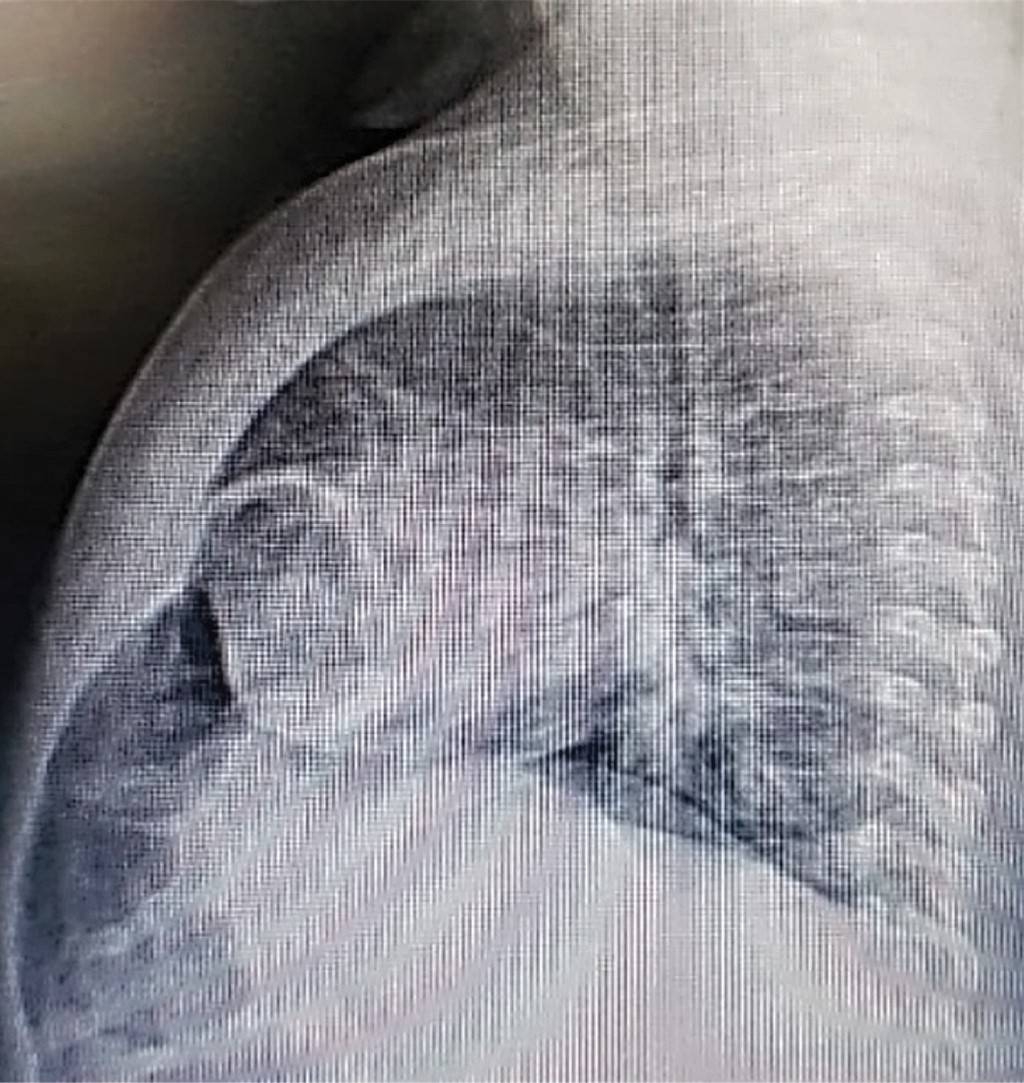

Paciente femenino de 13 meses, originaria y residente de Bogotá, Colombia. El abuelo paterno con diagnóstico de síndrome de Down. Ingresó en compañía de su madre, quien refirió un cuadro clínico de siete días de evolución caracterizado por tos productiva, no emetizante, no cianosante, acompañada de rinorrea hialina y fiebre de 38 oC. Acudió a urgencias de un centro de salud de primer nivel de atención, donde la encuentran con desaturación y aumento de trabajo respiratorio, por lo que indican oxígeno suplementario. Se sospechó neumonía. En biometría hemática se evidencia leucocitosis con neutrofilia, así como anemia microcítica hipocrómica. En Rx de tórax se observó imagen redondeada radiolúcida, con borde radiopaco bien delimitado, lo cual se identificó como hernia diafragmática anterior. Se inició tratamiento con penicilina cristalina. Dado que la paciente presenta deterioro clínico, se decide trasladarla a un centro de salud de mayor complejidad.

En el examen físico a su ingreso a la institución especializada, se encontró en buenas condiciones generales, peso de 10.2 kg, talla de 76 cm, con estado nutricional normal (acorde a las curvas de crecimiento para niños con síndrome de Down), con dificultad respiratoria leve, desaturación que se corregía con oxigenoterapia a bajo flujo. En la exploración del tórax se detectó presencia de crépitos finos en ambas bases pulmonares. Al revisar la Rx de tórax se corrobora diagnóstico de hernia diafragmática, pero sin datos de neumonía.

Al segundo día de ingreso, el servicio de Cirugía Pediátrica confirma que la hernia diafragmática anterior (Figuras 1 y 2) es de tipo HM, y consideran manejo quirúrgico. Al tercer día se corrige por laparoscopía, sin complicaciones. La evolución postquirúrgica fue favorable.

Figura 2